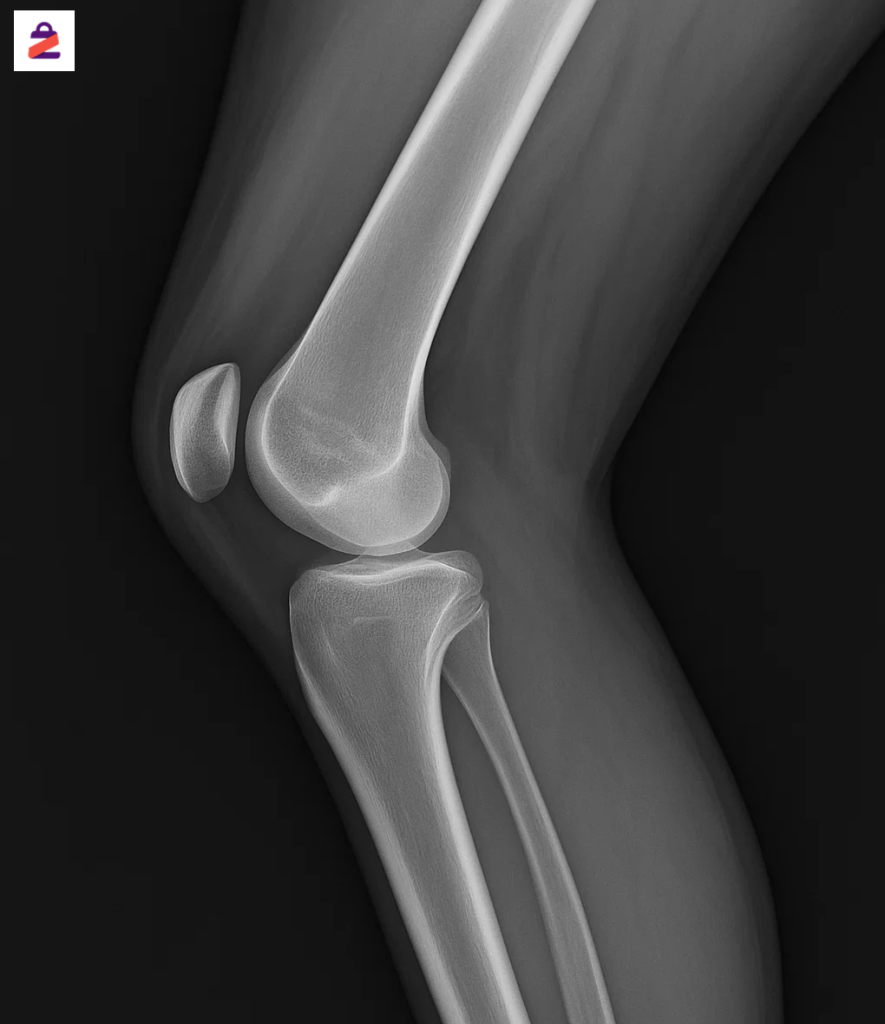

تصویربرداری

در برخی موارد، برای بررسی دقیقتر وضعیت مفصل و تشخیص شدت عقب زدگی زانو، پزشک از روشهای تصویربرداری استفاده میکند. رادیوگرافی ساده میتواند زاویه بین استخوان ران و درشتنی را در حالت ایستاده نشان دهد و مشخص کند که آیا هایپراکستنشن از نوع استخوانی است یا فقط به دلیل ضعف عضلانی اتفاق میافتد.

در موارد پیچیدهتر، MRI نیز ممکن است برای ارزیابی سلامت رباطها (بهویژه ACL) و بافت نرم اطراف زانو تجویز شود.

تصویربرداری به پزشک کمک میکند تا:

- زاویه دقیق رکورواتوم زانو را اندازهگیری کند.

- آسیب یا کشیدگی رباط صلیبی قدامی (ACL) را بررسی کند.

- تغییرات احتمالی روی سطوح غضروفی مفصل را شناسایی کند.

- برنامه درمانی دقیقتری برای بیمار تنظیم کند.